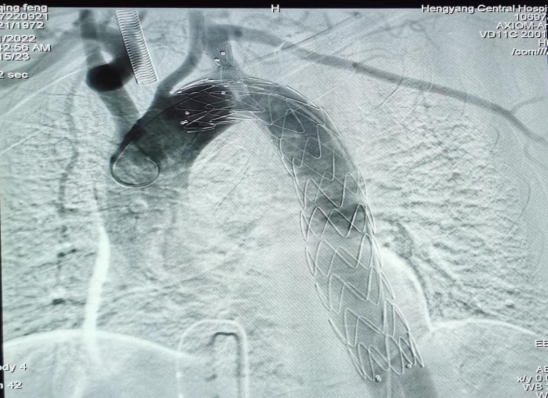

疾病的兇險與手術(shù)費的昂貴,讓許先生一家人左右為難。了解許先生經(jīng)濟(jì)困難,心血管中心趙慶禧主任醫(yī)師與患者充分溝通后,決定放棄傳統(tǒng)的穿刺方法(需使用血管縫合器),行股動脈和左側(cè)肱動脈切開入路,既保證了手術(shù)安全性又兼顧了經(jīng)濟(jì)性。最終在9月21日,許先生愿意接受介入微創(chuàng)治療。趙慶禧帶領(lǐng)介入團(tuán)隊和麻醉科團(tuán)隊密切配合,為其施行全麻下行“Castor分類型覆膜支架植入術(shù)”。僅在患者的左肱動脈,右股總動脈處分別做不到1cm的小切口,然后在DSA引導(dǎo)下精確定位,釋放覆膜支架一枚,保住鎖骨下動脈的同時也堵住了主動脈內(nèi)膜破口,手術(shù)歷時三個小時,順利完成,“致命炸彈”被徹底拆除,術(shù)后許先生恢復(fù)良好,于住院的第30天順利出院。

(術(shù)中釋放的一體式覆膜支架)